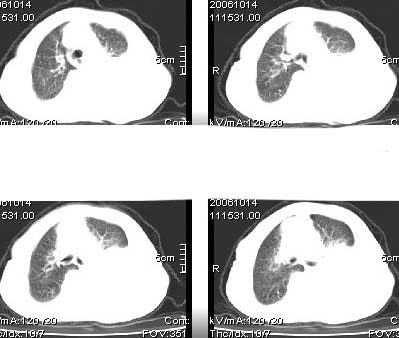

标题: CT4907:[原创]胸部平扫,请讨论!谢谢!!

考虑:左侧大量胸腔积液伴下叶压迫性且不张。

中央型肺癌,下叶不张,胸水

左侧大量胸腔积液伴下叶压迫性且不张,心包积液,左下叶支气管变窄,建议增强扫描,排除占位

左侧大量胸腔积液伴左下肺不张,左侧支气管狭窄,左舌段有膨胀感,中央型肺癌待排,心包有少量液体。肝顶部低密度影,需进一步检查

左侧大量胸腔积液伴左下肺不张,左侧支气管狭窄,左舌段有膨胀感,中央型肺癌待排,心包有少量液体

左侧大量胸腔积液,左下叶受压不张,纵隔向右侧轻移位,虽未见明显骨质破坏,但临床有刺激性咳嗽、胸疼等都支持非善类病变,应穿刺抽液细胞学检查,考虑右肺癌并胸膜转移。肝顶部似有低密度影,可进一步检查,排除转移灶。

患者以抽胸水到上级医院作细胞学检查,肝右顶部的确是{患者以作b超:囊性低密度区,考虑囊肿?}病灶。我的初步意见是考虑是左侧中央型肺癌。

1、高度怀疑:左肺中央型肺癌伴肺不张、胸水;

2、肝上病灶暂考虑囊肿。

3、心包内脂肪影清晰,未见积液。

左侧大量胸腔积液伴左下肺不张,左侧支气管狭窄,左舌段有膨胀感,中央型肺癌待排.